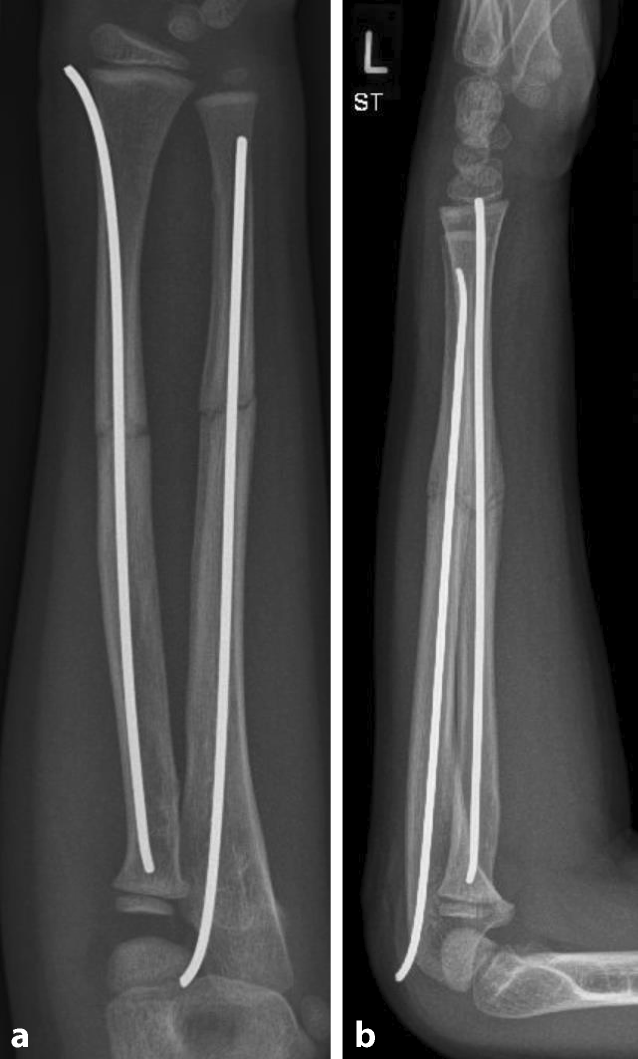

Abb. 4

Refraktur 10 Wochen nach initialer Fraktur durch Sturz vom Sofa. ab Unfallröntgen in zwei Ebenen

Abb. 5

Geschlossene Reposition und Versorgung mithilfe der elastisch-stabilen intramedullären Nagelung (ESIN). a a.p. Aufnahme, b seitliche Aufnahme